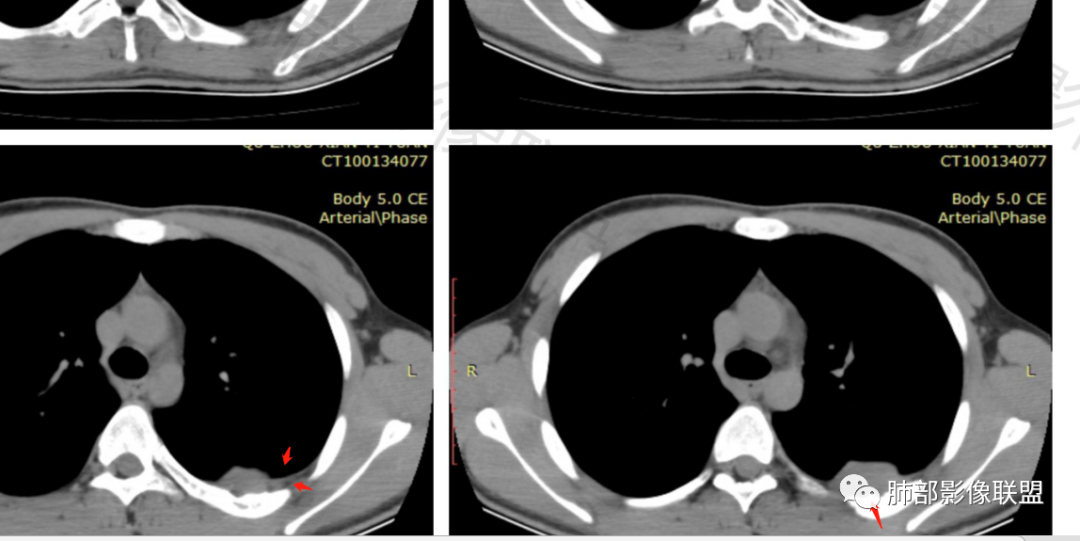

叶裂有变异,但病灶骑跨在叶裂上,外侧宽基底与胸壁相连,呈D子征

胸膜尾

病灶附近骨膜增厚、钙化

病灶明显突入胸壁,位于胸膜外

2.左侧叶间裂后缘及胸壁区不规则块影,肺组织一侧边缘光整。密度不甚均匀,未见钙化,不均匀强化,未见明确支气管及肺血管影进入,也未能显示肋间动脉进入。

3.块影有沿胸膜生长蔓延趋势,可见胸膜尾征。胸壁侧边界不清,所经两处肋骨内侧缘骨皮质吸收破坏,局部硬化,边界可分辨。肋骨未见变形膨胀或葱皮样骨膜反应。注意没有胸水。

2.块影沿胸膜生长蔓延,胸膜尾征,肺组织一侧边缘光整,未见支气管及肺血管影进入等也提示病灶位于肺外。

3.块影胸壁侧边界不清,肋骨破坏(肺单纯外压),提示具有一定侵袭性。肋骨未见膨胀,局部硬化,未见明确层状骨膜反应等,尽管骨外包块较大,即便患者年轻也不支持骨尤文肉瘤(Askin 瘤或PNET等),尤文肉瘤不具成骨能力。